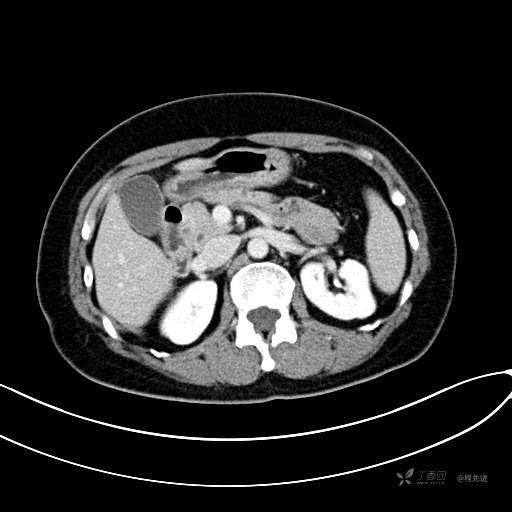

CT平扫